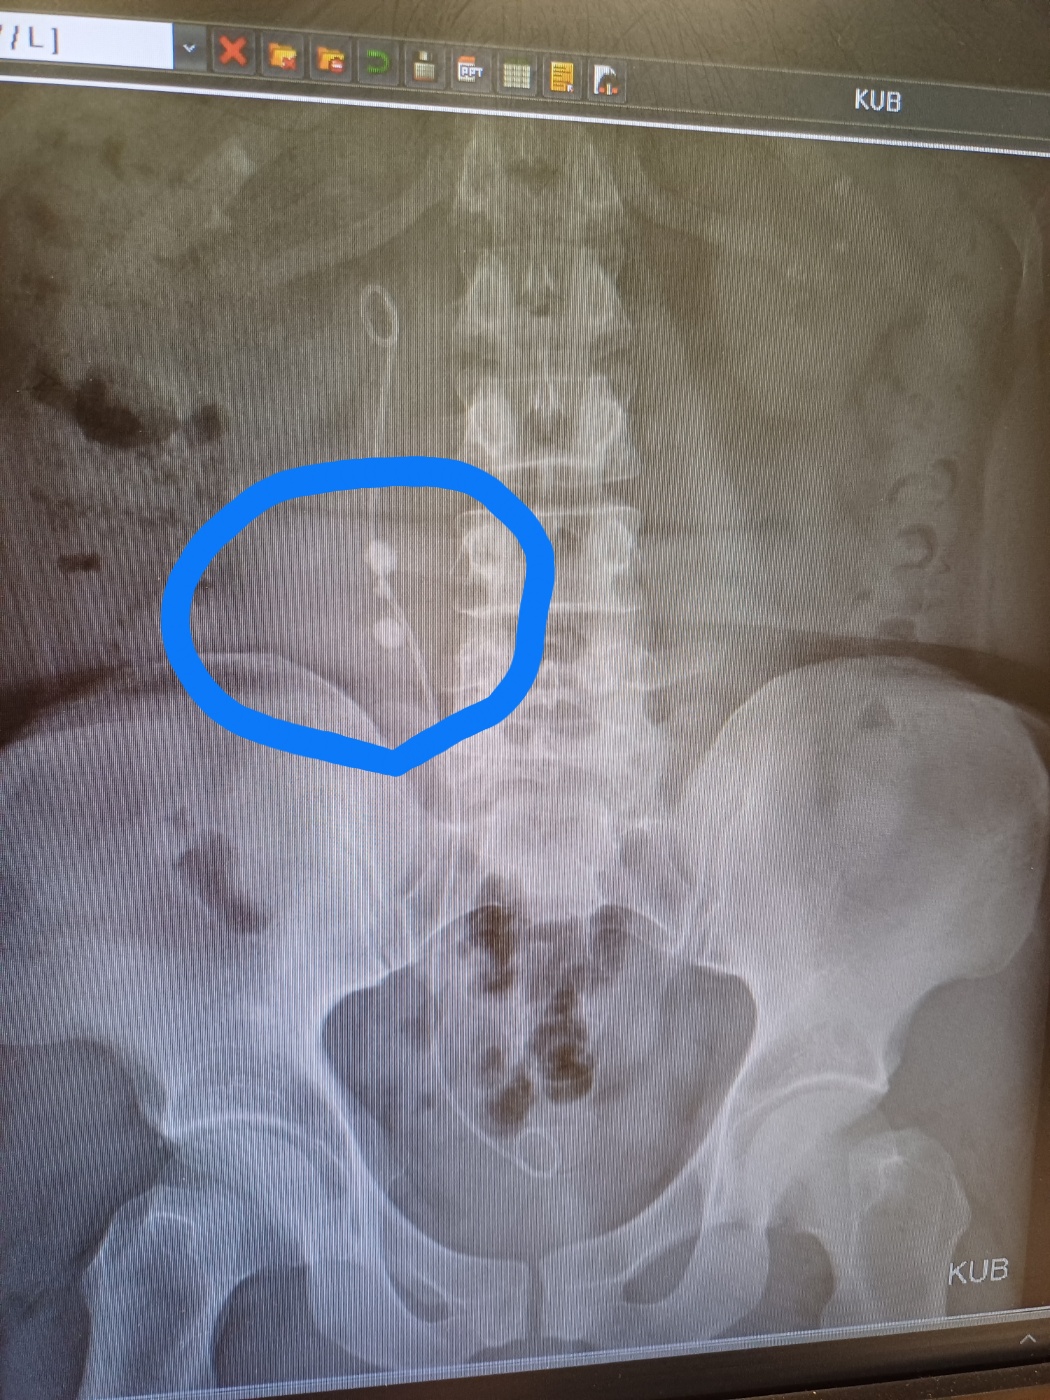

Á¦¸ñ ¿äÁò ³²ÀÚµé ¿ä·Î°á¼® Á¦°Å ½Å±â¼ú ÀÇ·á¹ý [59]

³ª.. ¿¹Àü¿¡ »« ¿äµµ°á¼®.. Àú°Å ¿äµµ·Î ³ª¿È ¤»¤»¤» Àú°Å »¬¶§.. ¿ÀÁÜ 3ÀÏ ¸ø´²¼­ ÇǺΰ¡ º¸¶ó»öÀ¸·Î ¹Ù²î´øµ¥ ¤»¤»¤» »©°í³­µÚ¿¡ 2kg ºüÁü.. ¸·Çû´ø ¼Òº¯ÀÌ ³ª¿Ã¶§ ±× Äè°¨Àº ÀØÀ»¼ö°¡ ¾ø¾ú´Ù.. ¼ö¾Ð½Ú °í¹«È£¼ö ¹°³ª¿Ã¶§ ¿Ô´Ù¸®°¬´Ù¸® ÅжóµíÀÌ °íÃò¿¡¼­ ¹°À̳ª¿Í¼­ ÁÂ¿ì ¶§¸®´Âµ¥ ÆÒƼ ¹ÙÁö ¿ÀÁÜ ¹¯´Â°Íµµ ¸ô¶ú´Âµ¥ ¤»¤» [2]

³ª.. ¿¹Àü¿¡ »« ¿äµµ°á¼®.. Àú°Å ¿äµµ·Î ³ª¿È ¤»¤»¤» Àú°Å »¬¶§.. ¿ÀÁÜ 3ÀÏ ¸ø´²¼­ ÇǺΰ¡ º¸¶ó»öÀ¸·Î ¹Ù²î´øµ¥ ¤»¤»¤» »©°í³­µÚ¿¡ 2kg ºüÁü.. ¸·Çû´ø ¼Òº¯ÀÌ ³ª¿Ã¶§ ±× Äè°¨Àº ÀØÀ»¼ö°¡ ¾ø¾ú´Ù.. ¼ö¾Ð½Ú °í¹«È£¼ö ¹°³ª¿Ã¶§ ¿Ô´Ù¸®°¬´Ù¸® ÅжóµíÀÌ °íÃò¿¡¼­ ¹°À̳ª¿Í¼­ ÁÂ¿ì ¶§¸®´Âµ¥ ÆÒƼ ¹ÙÁö ¿ÀÁÜ ¹¯´Â°Íµµ ¸ô¶ú´Âµ¥ ¤»¤»

skylamp

ÀÌ·± °¡Â¥ Á¤º¸Á» ÆÛ¶ß¸®Áö ¸¶¼¼¿ä. Àú°Ç ¹æ±¤°á¼® ºÐ¼âÇÑ µÚ ±× Á¶°¢µéÀ» »©³»´Â ¿µ»ó °°³×¿ä. Àú·¸°Ô syringe ·Î »©°Å³ª Ellick À̶ó´Â °ÍÀ¸·Î »©³À´Ï´Ù. ¿ä°ü°á¼®À̳ª ½ÅÀå°á¼®Àº Àú·¸°Ô ÇØ°á ¸øÇØ¿ä.